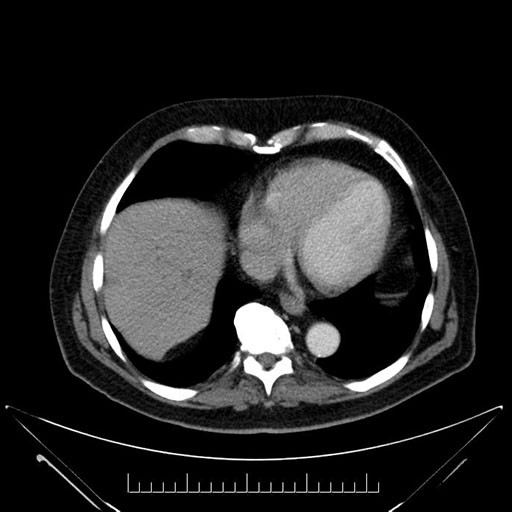

Axial - stented